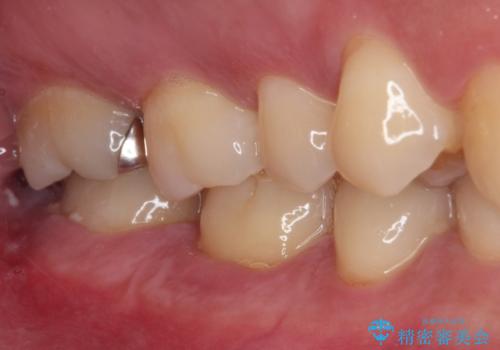

ゴールドインレーは銀歯のインレーやセラミックインレーと比べ、「技工操作の精度が高く、適合が著しく良い」というメリットがあります。特に上の奥歯は歯科医師の操作が行いにくいため、「適合の良さ」は再治療のリスクを防ぐ上でとても重要な要素となります。

上の奥歯は金属色が見えることもないため、審美的な問題は全くありません。